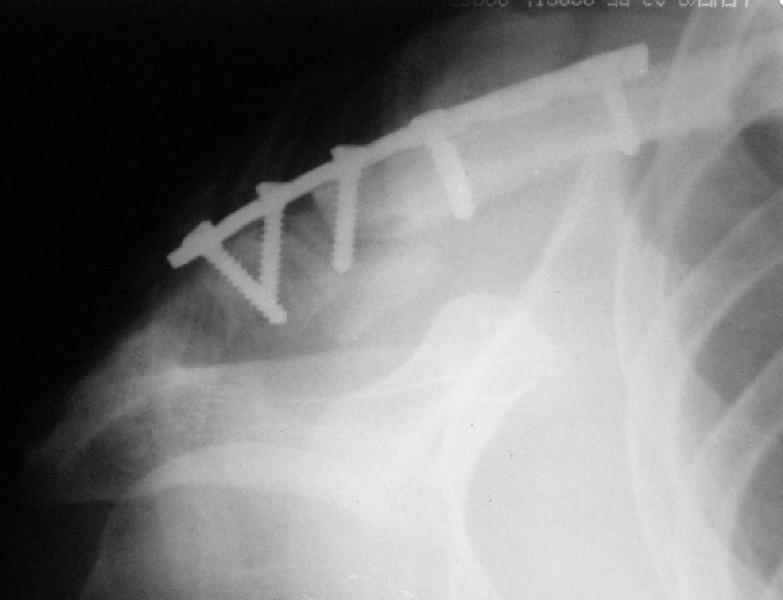

Сегодня прооперировал больного - накостный остеосинтез реконструктивной пластиной с ааллотендопластикой кл-кл связки.

На операции - обширная межотломковая ткань - мобилизовал проксимальный отломок без иссечения м-отломк.ткани, резекция выступающего конца( в последующем использовал как трансплантат).